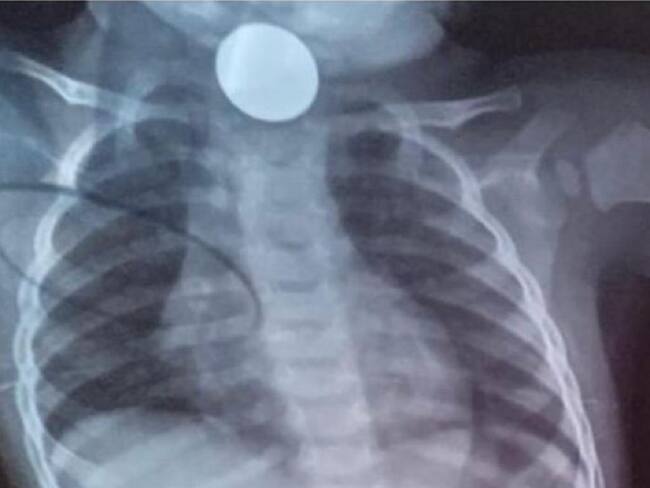

Un bebé que se tragó una moneda de manera accidental hace 8 días, al parecer la EPS AsmetSalud, se niega a atenderlo en Manizales y se esperaría fuera traslado hacia el municipio de Dosquebradas, Risaralda, para realizarle una intervención quirúrgica.

Se espera que, el pequeño sea trasladado hasta el municipio de Dosquebradas, en el departamento de Risaralda para realizarle una intervención quirúrgica de manera inmediata.